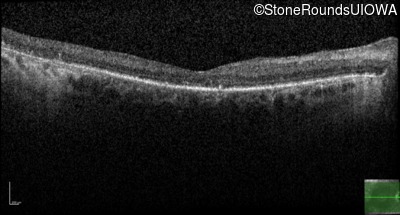

Age at visit: 59 years